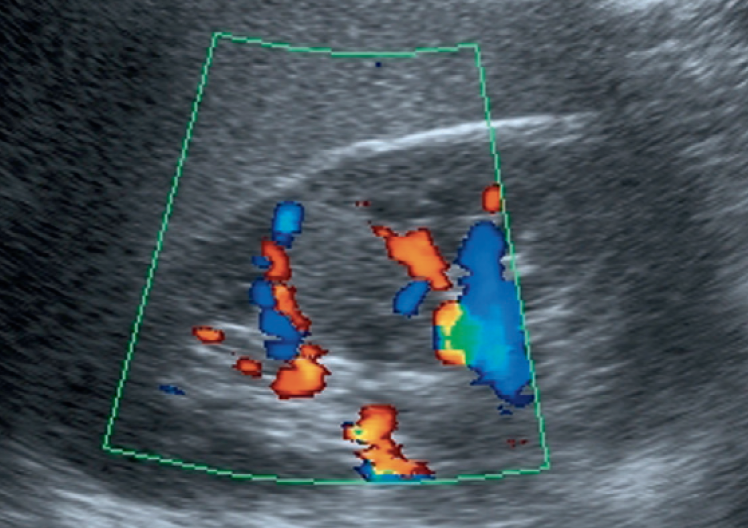

أعتقد بأن هذا من أهم المتغيرات التي قد يشتبه في كونها ورم. هي ببساطة تضخم لنسيج الكلية parenchyma إلى الداخل sinuses مرورا بين الأهرامات الكلوية medullary pyramids.

يميزه تناسق echogenicity بينه وبين باقي parenchyma بالإضافة لعدم وجود ارتفاع أو تغير ملحوظ في قراءات colour Doppler. غالبا لا يزيد عرضه عن ٣ سم.